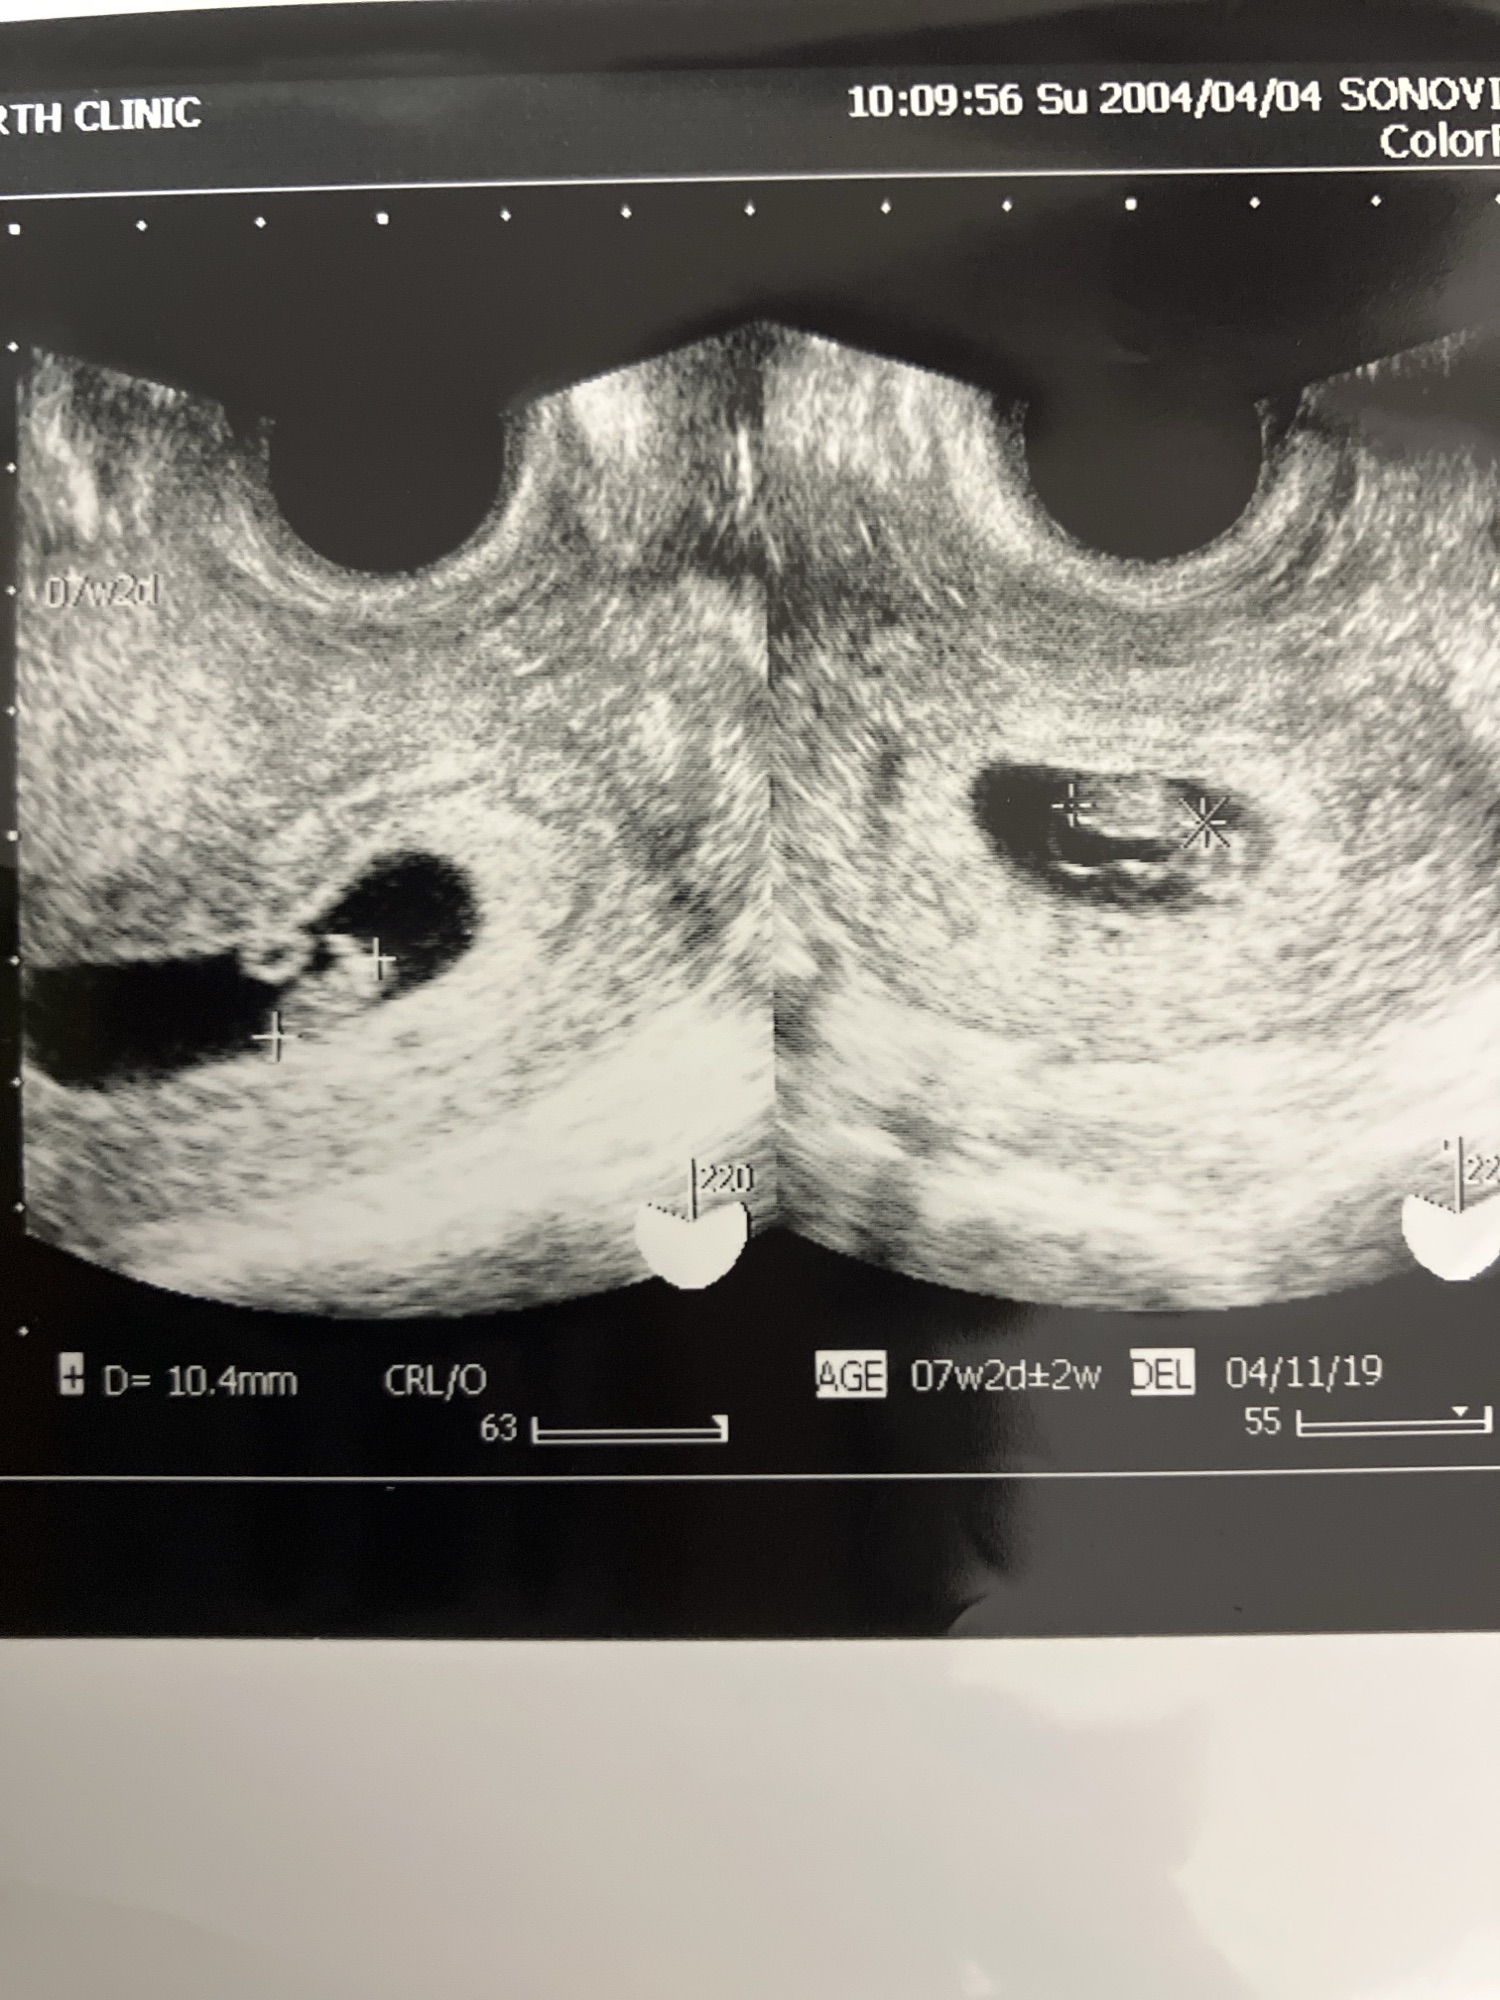

2度目の診察 前回はまだ双子の可能性が高…